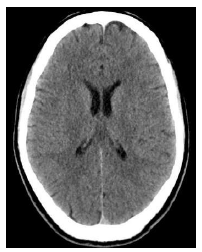

Um homem de quarenta anos de idade, em situação de rua, foi levado pelo SAMU ao hospital, devido a rebaixamento do nível de consciência em via pública. Na admissão, foram verificados sinais de desnutrição importante, hálito etílico e glicemia de 25 mg/dL. O paciente foi tratado exclusivamente com glicose endovenosa, evoluindo com melhora do nível de consciência e surgimento de confusão mental, nistagmo e ataxia.

Foi realizada uma tomografia de crânio, cujo resultado está representado abaixo.

Com relação ao caso clínico acima, assinale a alternativa que apresenta, respectivamente, o diagnóstico mais provável e o tratamento indicado ao paciente.